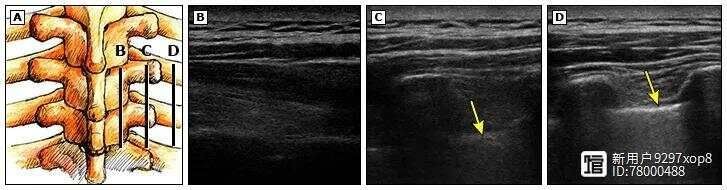

图1 左侧图显示了胸椎旁阻滞期间超声换能器的不同位置和方向,与右侧图像相对应。

当换能器横向放置时,胸膜清晰可见。

当换能器放置在更内侧且与皮肤成相同角度时,看不到胸膜。

将换能器放置在内侧但横向倾斜以优化入射角,胸膜清晰可见。

图2 该图显示了椎板 (B)、横突 (C) 和肋骨 (D) 水平的超声图像,超声换能器处于矢状方向。请注意,胸膜(箭头)在侧面更浅且更亮。